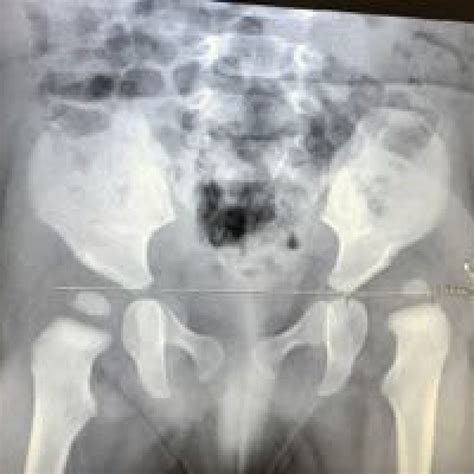

Diagnosing displasia de cadera typically involves a combination of physical examinations and imaging tests. The diagnostic process may include:

• Physical Examination: A healthcare provider will assess the range of motion in the hip joint and look for signs of instability or misalignment.

• Imaging Tests: X-rays, ultrasounds, or MRI scans may be used to visualize the hip joint and confirm the diagnosis.

In infants, ultrasound is often the preferred imaging method because it does not expose the baby to radiation and can provide detailed images of the soft tissues around the hip joint.